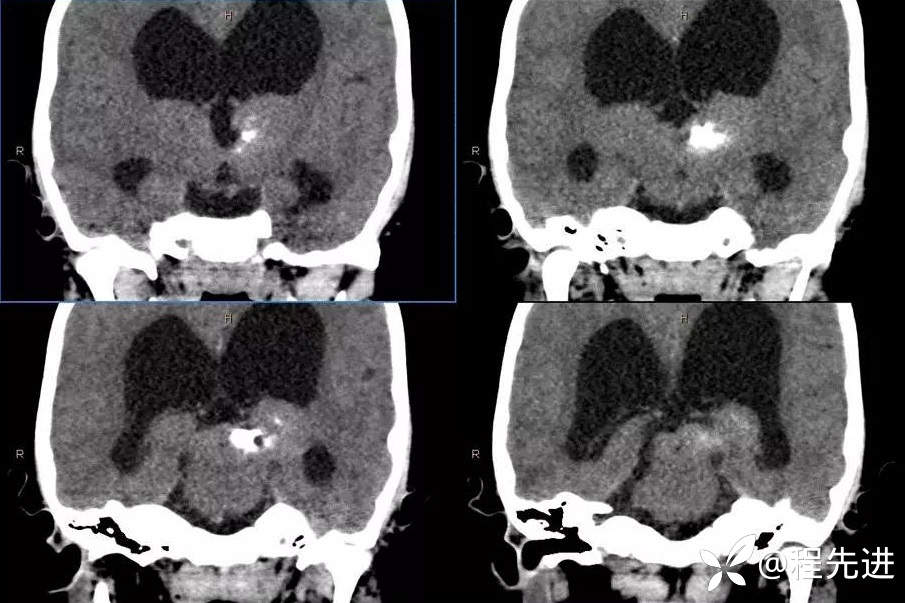

CT